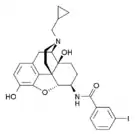

The pharmacodynamic response to an opioid depends upon the receptor to which it binds, its affinity for that receptor, and whether the opioid is an agonist or an antagonist. For example, the supraspinal analgesic properties of the opioid agonist morphine are mediated by activation of the μ1 receptor; respiratory depression and physical dependence by the μ2 receptor; and sedation and spinal analgesia by the κ receptor. Each group of opioid receptors elicits a distinct set of neurological responses, with the receptor subtypes (such as μ1 and μ2 for example) providing even more [measurably] specific responses. Unique to each opioid is its distinct binding affinity to the various classes of opioid receptors (e.g. the μ, κ, and δ opioid receptors are activated at different magnitudes according to the specific receptor binding affinities of the opioid). For example, the opiate alkaloid morphine exhibits high-affinity binding to the μ-opioid receptor, while ketazocine exhibits high affinity to ĸ receptors. It is this combinatorial mechanism that allows for such a wide class of opioids and molecular designs to exist, each with its own unique effect profile. Their individual molecular structure is also responsible for their different duration of action, whereby metabolic breakdown (such as N-dealkylation) is responsible for opioid metabolism.

Several semi-synthetic opioids were developed in Germany in the 1910s. The first, oxymorphone, was synthesized from thebaine, an opioid alkaloid in opium poppies, in 1914.[228] Next, Martin Freund and Edmund Speyer developed oxycodone, also from thebaine, at the University of Frankfurt in 1916.[229] In 1920, hydrocodone was prepared by Carl Mannich and Helene Löwenheim, deriving it from codeine. In 1924, hydromorphone was synthesized by adding hydrogen to morphine. Etorphine was synthesized in 1960, from the oripavine in opium poppy straw. Buprenorphine was discovered in 1972.[228]